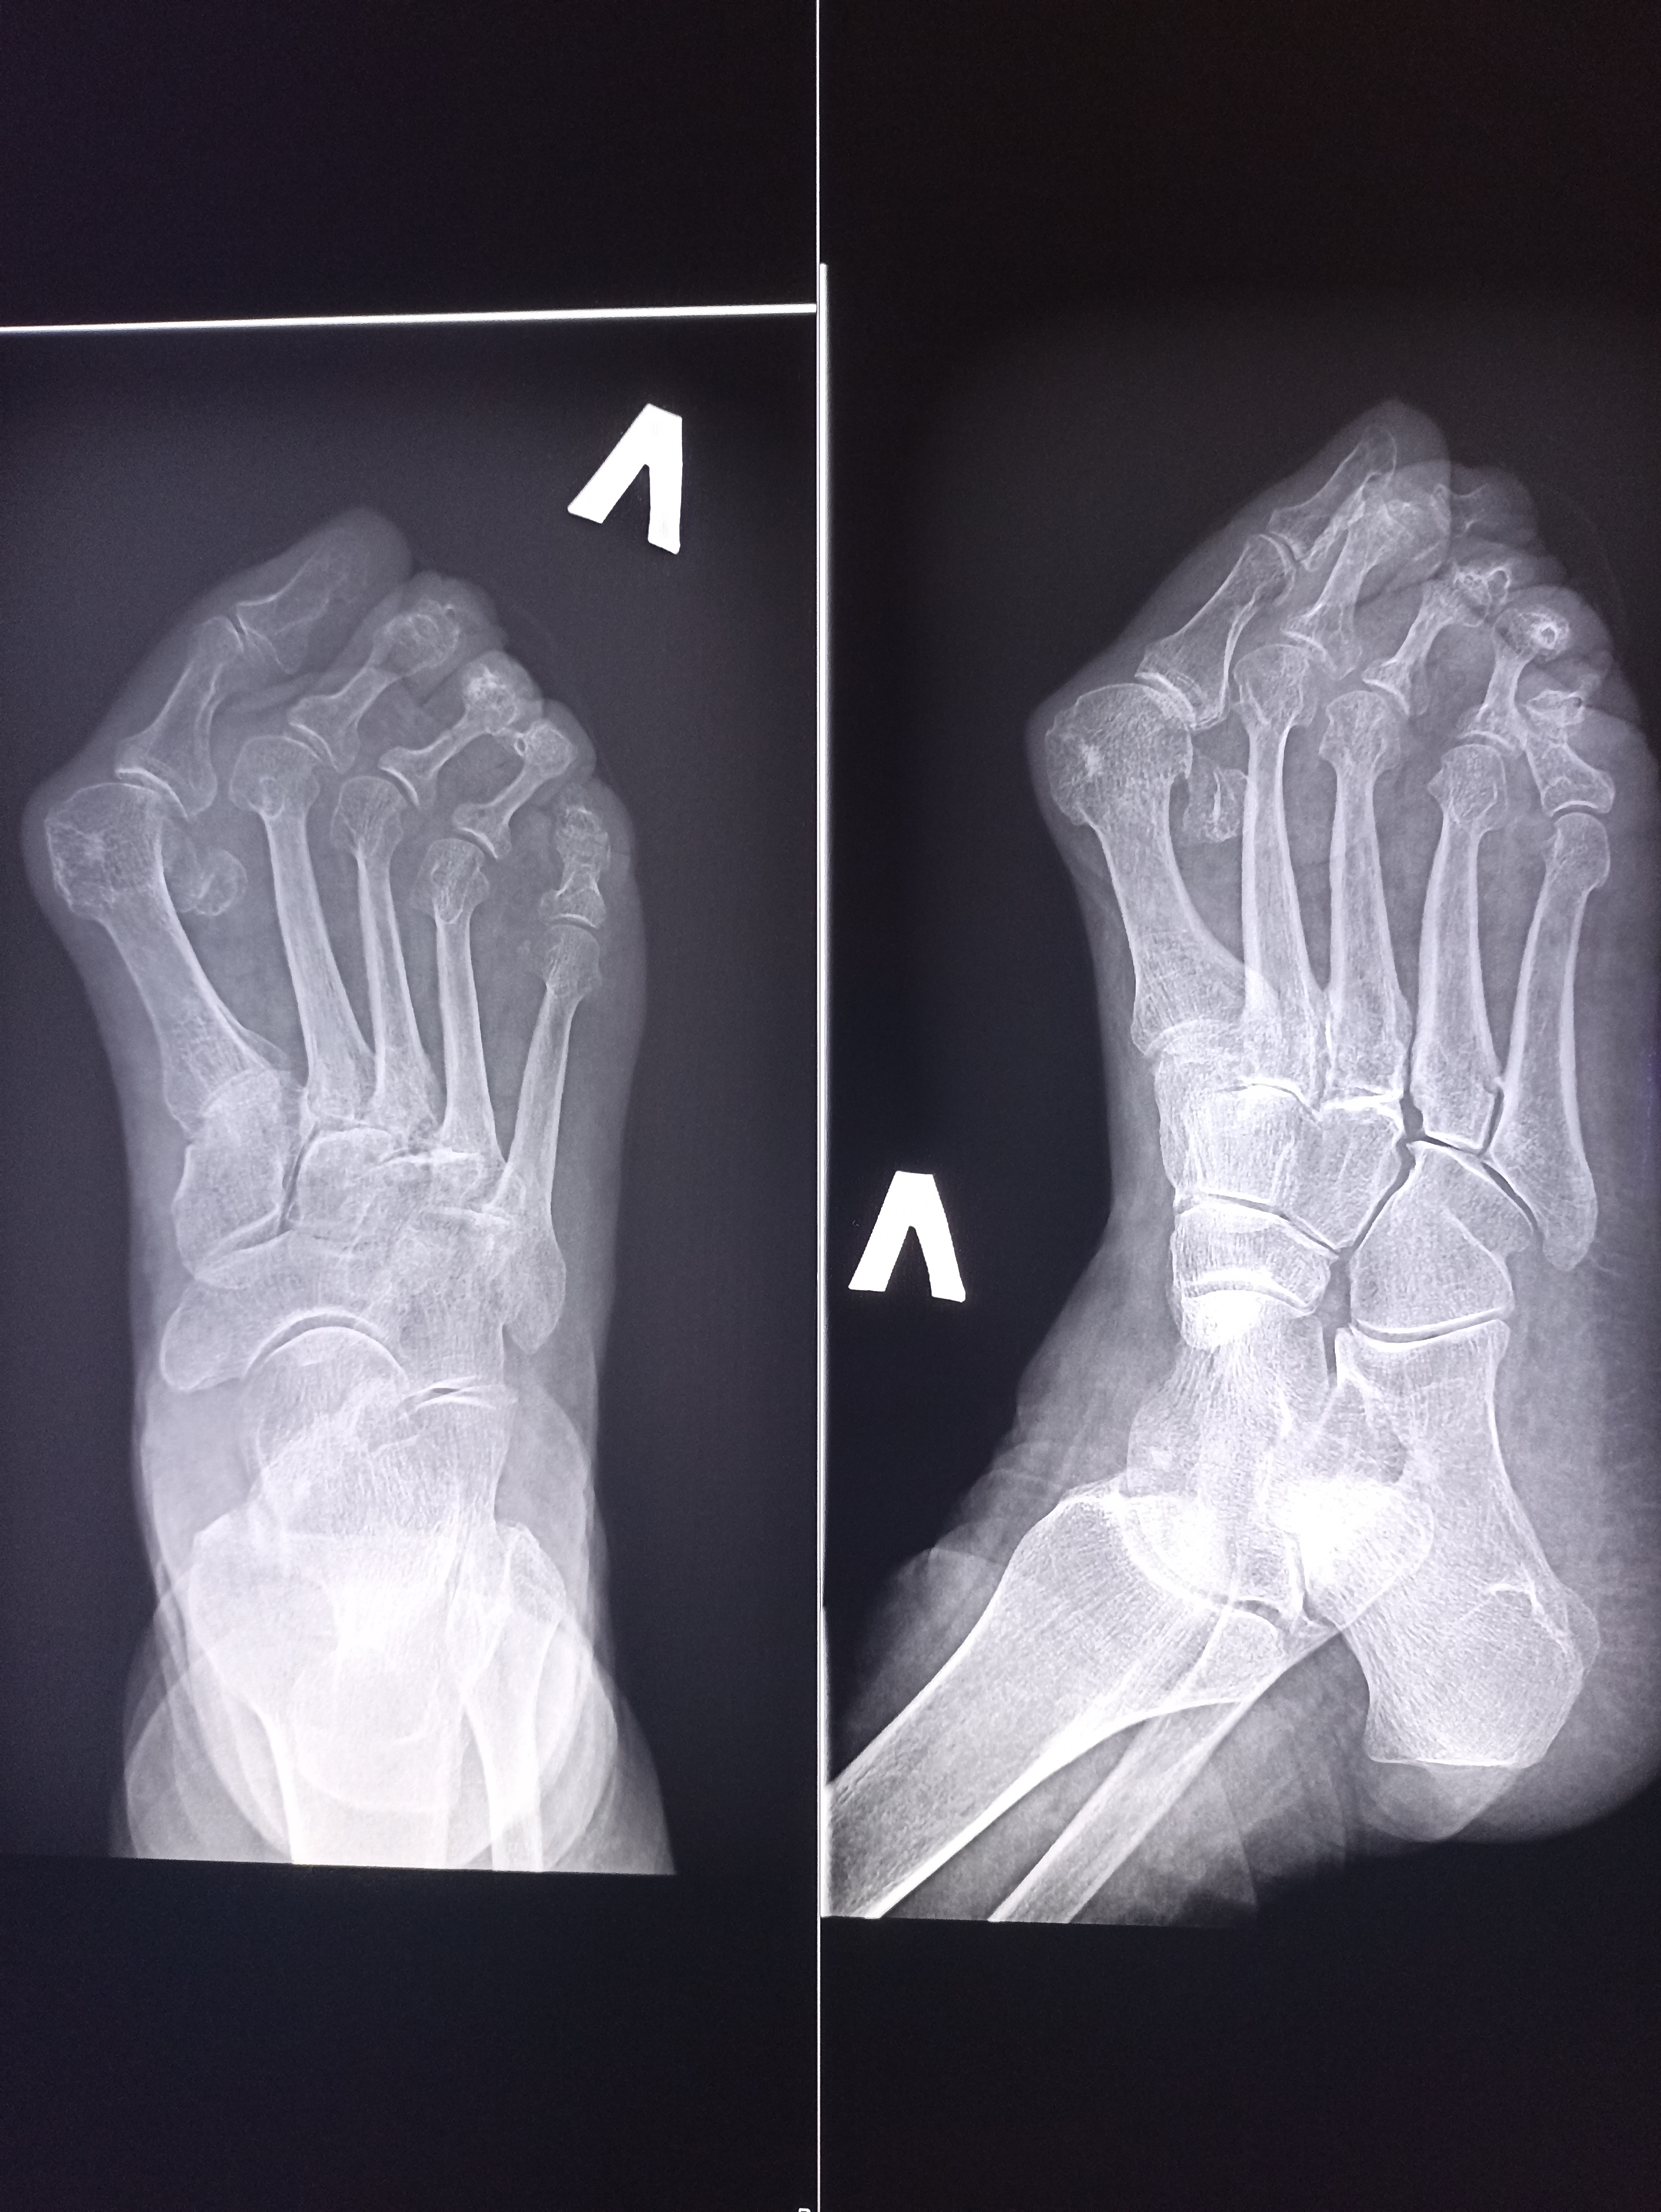

IMG20251014105834.jpg

Чо тут у нас?

Аноним 16/10/25 Чтв 08:43:03 #8 №325599234

>>325599083

Удар об угол дивана?

Аноним 16/10/25 Чтв 08:44:49 #9 №325599274

>>325599234

Ни, прост вальгусная деформация

Плов я вчера доел, в вс приготовил, а от макарошек я с диетической целью отрекся не могу контролировать их поедание :-(

Аноним 16/10/25 Чтв 09:18:08 #26 №325600117

>>325604511

да